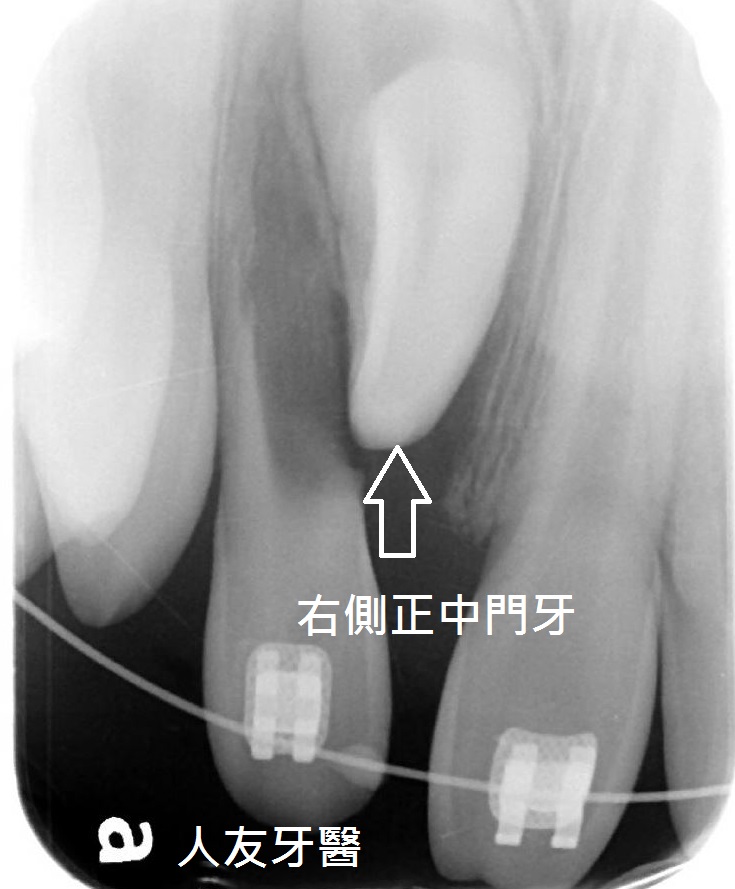

牙齒長不出來怎麼辦? part 1